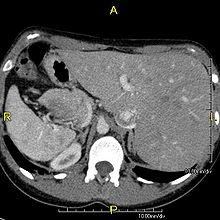

Effect on anatomy

The condition affects all major structures within the thorax and abdomen. Generally, the organs are simply transposed through the sagittal plane. The heart is located on the right side of the thorax, the stomach and spleen on the right side of the abdomen and the liver and gall bladder on the left side. The heart's normal right atrium occurs on the left, and the left atrium is on the right. The lung anatomy is reversed and the left lung has three lobes while the right lung has two lobes. The intestines and other internal structures are also reversed from the normal, and the blood vessels, nerves, and lymphatics are also transposed.

Diagnosis of situs inversus can be made using imaging techniques such as x-ray, ultrasound, CT scan, and magnetic resonance imaging (MRI).[6]